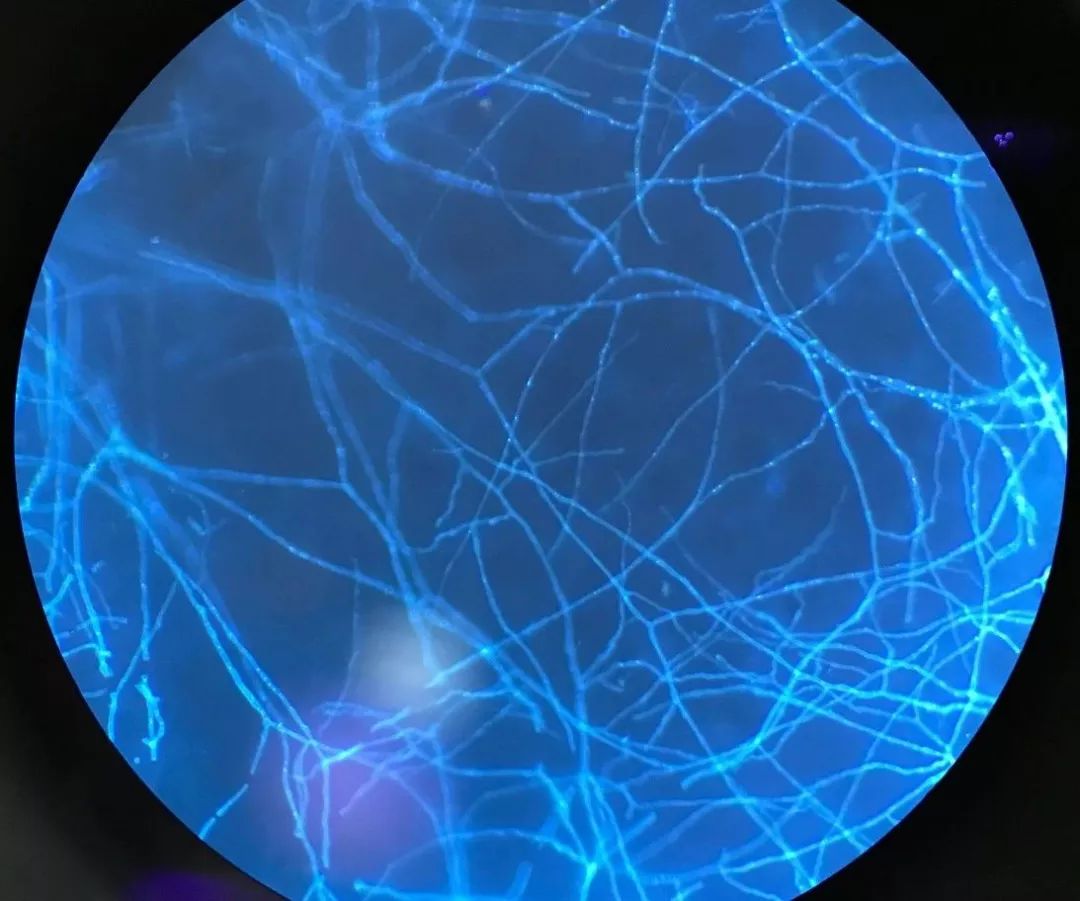

猫癣属于一种真菌性疾病,主要是由犬小孢子菌感染所致,还有一小部分是须毛癣菌感染,表现为圆形或椭圆形的皮疹,有瘙痒,该病原菌能够感染人类。除了猫以外,狗狗们也可以感染犬小孢子菌,从而传染人类。

当然是看医生了,要及时来院就诊,必要时进行真菌镜检,来帮助我们诊断!